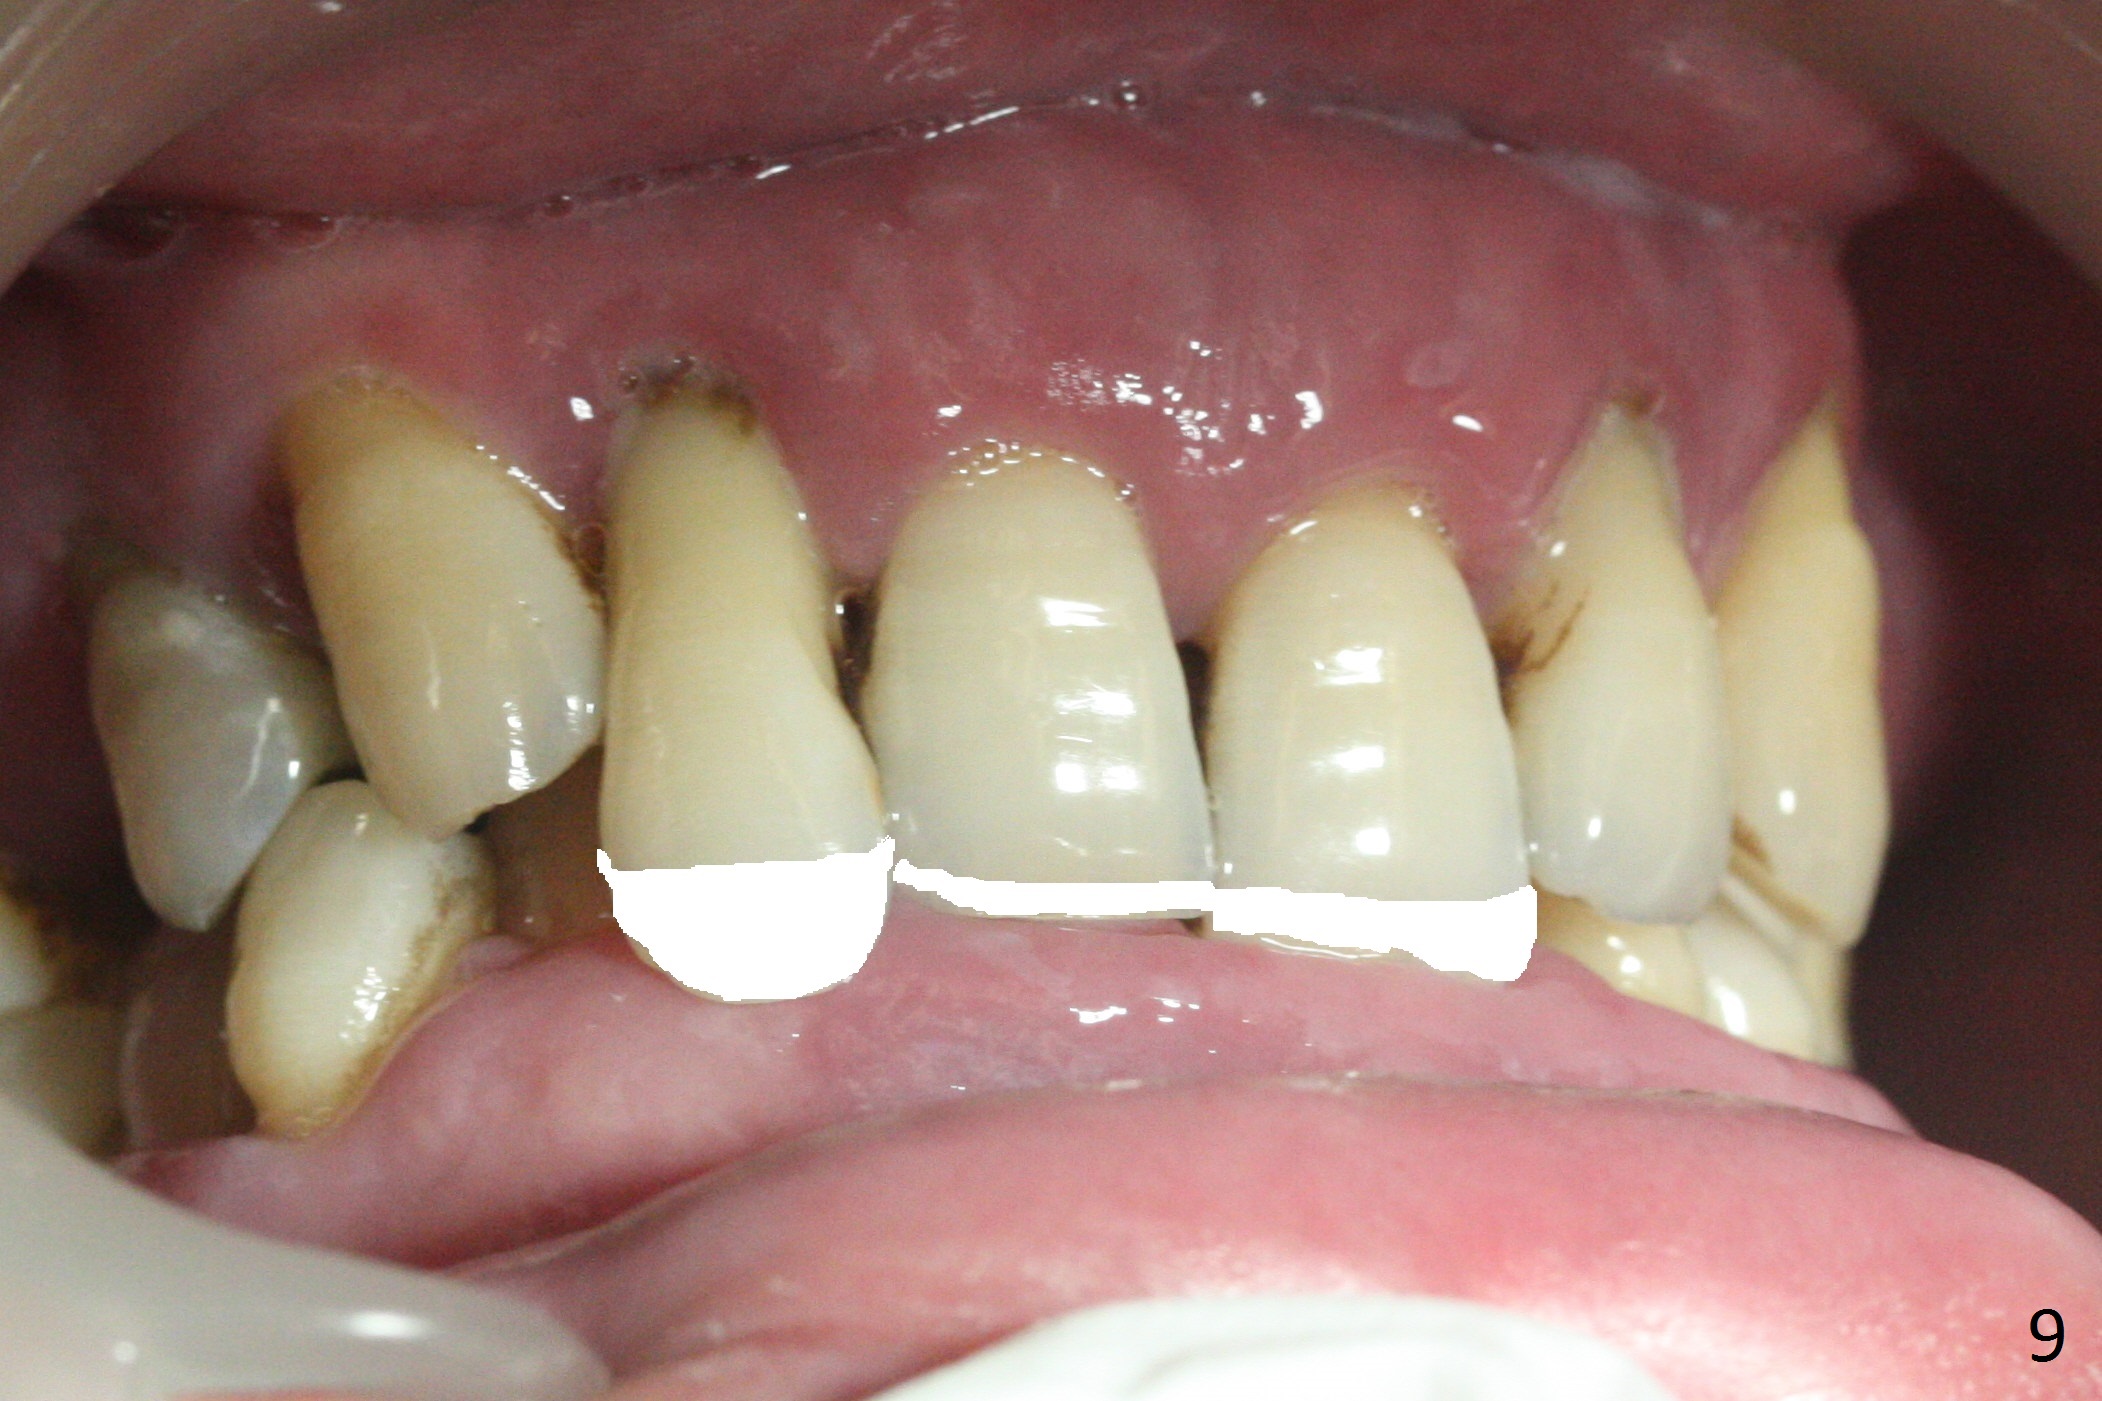

A 36-year-old man (ex-smoker) has advanced chronic periodontitis (Fig.1-5). His chief complaint is "I cannot chew on the right side now because of pain (Fig.1: #3 abscess <) and the bottom front teeth are loose (Fig.2,5: #23-26)". He has not masticated on the left side because of the mobile teeth. Due to finance, implants will be placed at #3,4 (Fig.12), 23 and 26 at the appointments of scaling & root planing.

Class II Division II malocclusion (Fig.2,6) will make it difficult to restore #23-26 implant-supported FPD. Although the teeth #7-10 may need to be replaced later (Fig.7,8), enameloplasty will be conducted for #7-10 (Fig.9 white area; Fig.12 black circles (gross reduction)) prior to #23-26 extraction and implant placement (Fig.10). To be flexible in restoration (angulation) and possible future hybrid denture, 2-piece narrow implants will be placed (3.0 or 3.3 mm) instead of 1-piece ones. In fact CBCT shows that the narrowest regular implant (3.8 mm) can be placed in the lower anterior region (Fig.13-15).